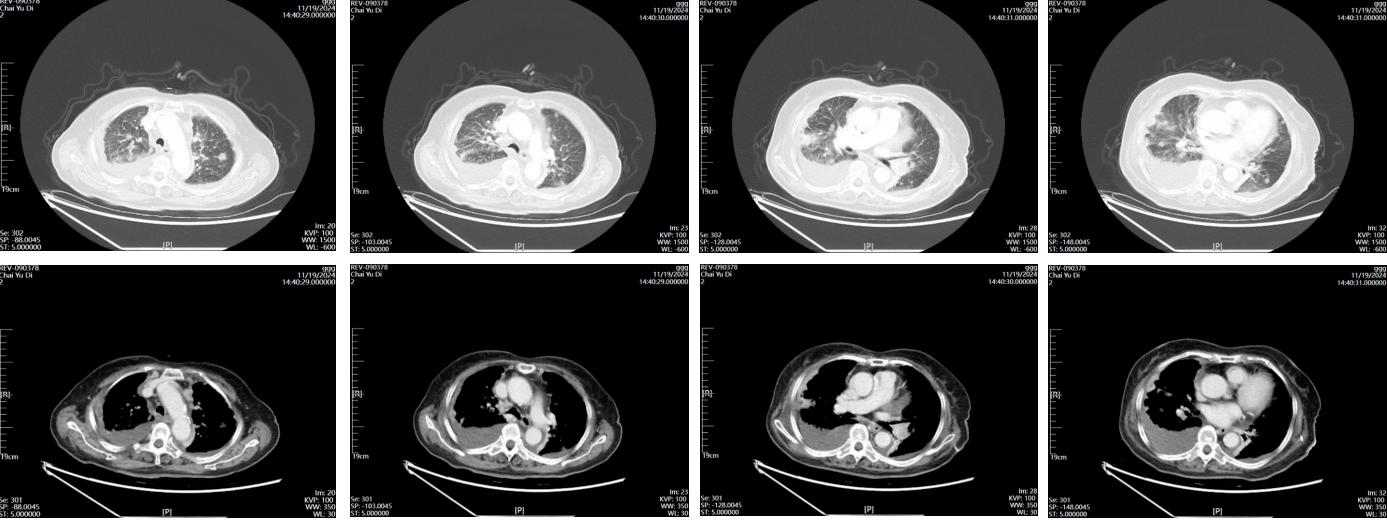

◾ 胸部CT示: 两肺弥漫结节,考虑转移,双侧胸膜转移可能;左肺上叶软组织影,双侧肺门增大,左肺支气管狭窄,左肺局部不张,双侧胸腔积液。

2024.11.14行PET-CT示:左肺上叶尖后段结节 FDG 代谢轻度增高,倾向恶性病变;纵隔(4R)及双肺门淋巴结FDG 代谢增高,倾向淋巴结转移,双侧胸膜(包含纵隔胸膜及叶间胸膜等)增厚 FDG 代谢轻度增高,倾向胸膜多发转移伴双侧胸腔少量积液,双肺多发结节部分 FDC 代谢轻度增双肺多发转移,右侧肩胛骨代谢增高灶,倾向骨转移。

2024.11.19胸部CT示:左肺上叶恶性肿瘤可能,双肺、双侧胸膜发转移灶,纵隔内多发稍大淋巴结;双侧少量胸腔积液伴双肺下叶局限性肺不张;主动脉及冠状动脉钙化。

图1 2024.11.19 胸部CT结果